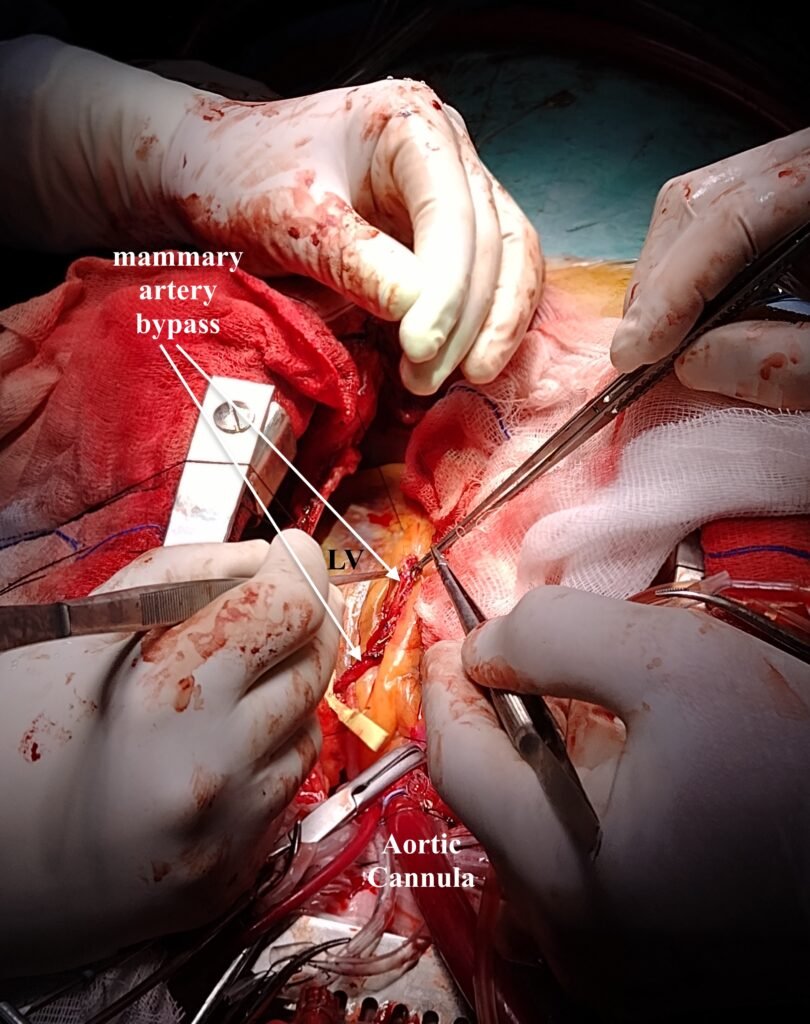

Vista desde la cabeza del paciente. Se ha abierto en forma amplia a la arteria descendnte anterior, enmarcada entre los asteriscos negros (*). Habitualmente la apertura no debe superar 1.5 veces el diámetro del vaso, mas en esta ocasión se realizó una apertura amplia del vaso a efectos de realizar una revascularización perfecta. En el óvalo se aprecia -en detalle y en general- a la arteria mamaria interna abierta y expuesta para su sutura.

la arteria mamaria interna (mammary artery bypass) señalada con flechas se halla suturada a la arteria descendente anterior casi en su totalidad.